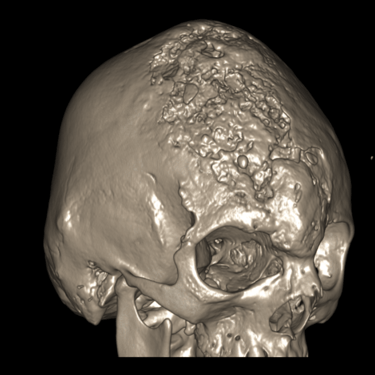

Osteomielitis Frontal | Diagnóstico por Tomografía

La osteomielitis frontal es una infección del hueso craneal que generalmente se origina como complicación de una sinusitis frontal no tratada o mal resuelta. Clínicamente puede manifestarse con dolor localizado, fiebre, edema frontal y signos inflamatorios en la región afectada. El método diagnóstico de elección es la tomografía computarizada (TC), que permite identificar destrucción ósea, engrosamiento cortical e incluso colecciones asociadas. Este estudio es esencial para diferenciarla de otras lesiones y planificar un tratamiento adecuado, que puede incluir antibióticos de amplio espectro y cirugía para drenar y desbridar el tejido infectado, evitando complicaciones intracraneales graves.